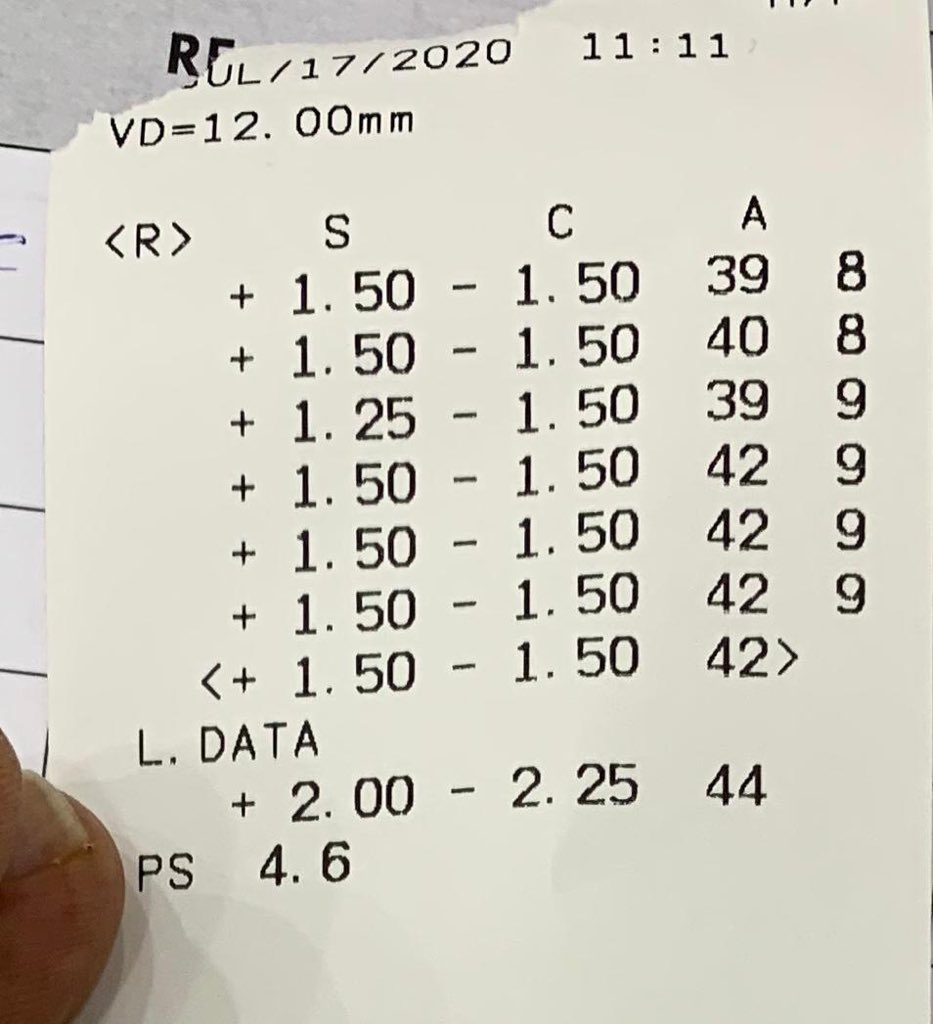

عمر المريض 32 سنه ، زار العياده قبل 4 سنوات ، معه قرنيه مخروطيه متقدمه ولكن من النوع الي نسميه Keratoglobus اي ان القرنيه محدبه ومخروطيه ولكن بشكل منتظم ، ينتج عنه قصر نظر شديد وانحراف قليل عكس حالات القرنيه المخروطيه التقليديه حيث يزيد الانحراف عن القصر في معظم الاحيان !!

في زيارته الاولى قبل 4 سنوات ، كان يستخدم عدسات لينه تقليديه قوتها تقريبا -10.00 درجات ، طبعا كونها اصلا غير ملائمه لسطح القرنيه المحدب كانت تتحرك كثير وتسبب جفاف والم واحمرار وكراهيه شديده للضوء ولكن كان يتحمل كل هالمعاناه لانها تعطيه نظر يقدر يمشي حاله فيه !!

القرار طبعا في تلك الفتره ، اولا يتوقف عن العدسات اللينه الغير ملائمه ، كورس ادويه عباره عن قطرات مرطبه ومضادات للتحسس وتجربه عدسات scleral ، بعد اسبوعين وعند وصول العدسات كانت العيون هدت شوي وبدت بمرحله التعافي مع استخدام العدسات الجديده والحمدلله مع نظر مميز ،،